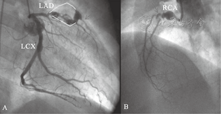

汇报病史:患儿入院后完善相关检查,肝肾功能及CK-MB、肌钙蛋白正常;第2天行左右冠状动脉造影术,显示左前降支主干巨大冠状动脉瘤形成,瘤体大小16 mm×38 mm,内见造影剂不规则充盈缺损,提示血栓形成,瘤体近端的左前降支无明显狭窄,远端主干重度狭窄仅见极少血供;左回旋支近分支处冠状动脉瘤形成,瘤体大小6.1 mm×9.5 mm,瘤体前后冠状动脉未见狭窄,远端血供好;右冠状动脉造影显示右冠状动脉主干近开口处冠状动脉瘤形成,瘤体大小8.8 mm×13.6 mm,瘤体前后冠状动脉均有狭窄,远端血供好(图3)。99mTc-心肌灌注显像显示:左室前壁及心尖局灶性缺血。

A. 左冠状动脉造影显示前降支(LAD)巨大冠状动脉瘤并血栓形成(黄色线框内),远端近乎闭塞(箭头);左回旋支(LCX)小型冠状动脉瘤(箭头),未见狭窄;B. 右冠状动脉造影显示右冠状动脉(RCA)主干冠状动脉瘤形成并远端狭窄(箭头)。